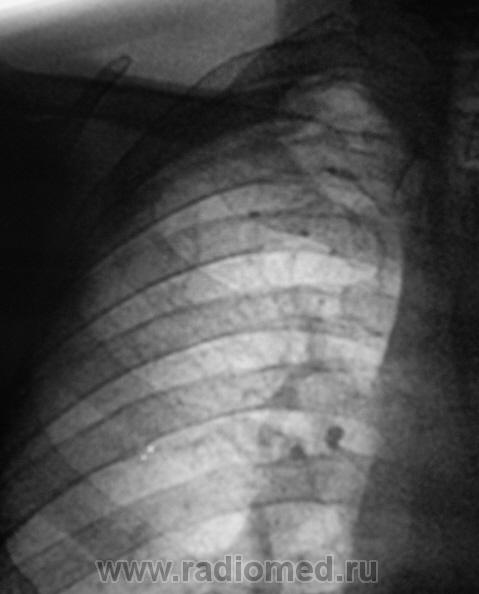

При расшифровки цифровых флюорограмм пациент "взят на контроль". Смутила правая верхушка и верхняя доля правого лёгкого.

Произведено дообследование.

Пациент направлен на консультацию к фтизиатру. Произведено общеклиническое дообследование, пациент госпитализирован в туб. большицу.